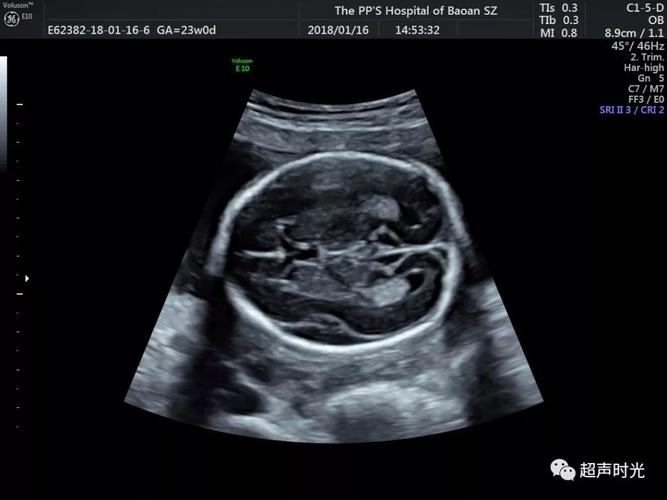

侧脑室宽度正常值,正常脑室图片

不管是8mm还是9mm,代表宝宝的侧脑室宽度是正常的

图一 正常侧脑室的标准切面.

讨论一下大排畸侧脑室正常值

单纯性轻度脑室扩张(宽度为10~12mm) 者大多结局正常,而合并其他异常

9cm(随访)的意思是脑室增宽数值接近高值了,需要定期的复查观察其变化